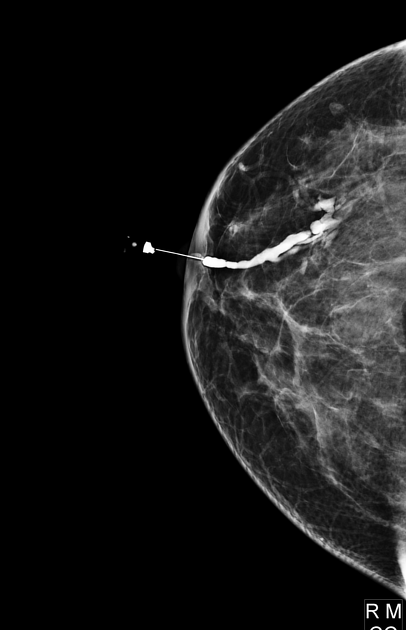

You can see radiographs and MRI images illustrating an intraductal papilloma below. Authors: Mohammad Taghi Niknejad, Bahman Rasuli. Source: Radiopaedia [11]:

4. Ductography is used to clarify the diagnosis. On radiographs, after contrast agent injection, duct dilation and deformity, irregularities of contours with the presence of contrasted formations and filling defect (disruption in the contrast enhancement pattern) are determined.